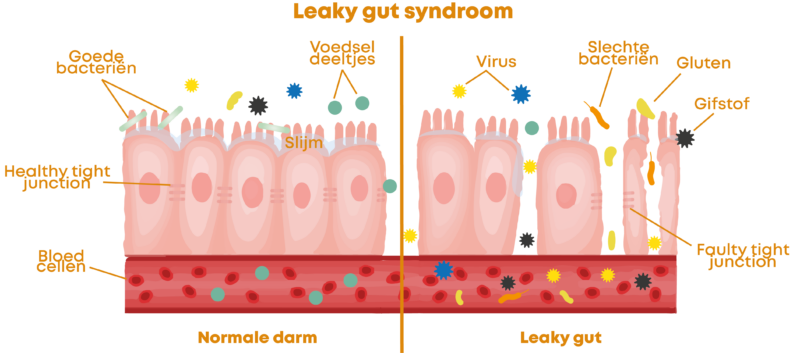

Mensen met leaky gut syndroom (doorlaatbare darmbarrière) hebben een aanzienlijk verhoogd risico op inflammatoire gewrichtsaandoeningen.

De reden?

De doorlaatbare darmbarrière zorgt ervoor dat ontstekingsstoffen in het bloed terechtkomen en vervolgens door het hele lichaam worden verspreid, rechtstreeks naar gewrichten, pezen, spieren en ligamenten.

Hoe de darmen je gewrichten kunnen verlammen

Ik zal het kort uitleggen:

70% van je immuunsysteem bevindt zich in de darmen.

Hier wordt besloten of ontstekingen onder controle worden gehouden – of dat ze uit de hand lopen.

Als de darmflora uit balans is – door stress, medicatie of voeding – gebeurt het volgende:

1. de slechte bacteriën verdringen de goede.

Slechte bacteriën vermenigvuldigen zich snel – vooral als je pijnstillers slikt, antibiotica slikt of een suikerrijk dieet volgt. Ze overwoekeren de goede bacteriën en nemen hun plaats in.

2. het darmslijmvlies wordt aangetast.

De slechte bacteriën produceren agressieve stofwisselingsproducten die het darmslijmvlies beschadigen. De beschermende barrière wordt poreus – als een zeef met gaten.

3. de darmbarrière wordt permeabel (lekkende darm).

Door het beschadigde slijmvlies kunnen nu stoffen in de bloedbaan terechtkomen die daar niet thuishoren: onverteerde voedseldeeltjes, bacteriële gifstoffen, ontstekingsstoffen …

4 Het immuunsysteem slaat alarm en reageert met ontstekingen.

Je lichaam herkent deze indringers als een bedreiging. Het start een ontstekingsreactie – niet alleen in de darmen, maar in het hele lichaam.

5 Deze ontstekingen migreren rechtstreeks naar de gewrichten.

De ontstekingsboodschappers circuleren in het bloed en hopen zich op in gewrichten, pezen, spieren en ligamenten. Daar veroorzaken ze pijn, zwelling en stijfheid.